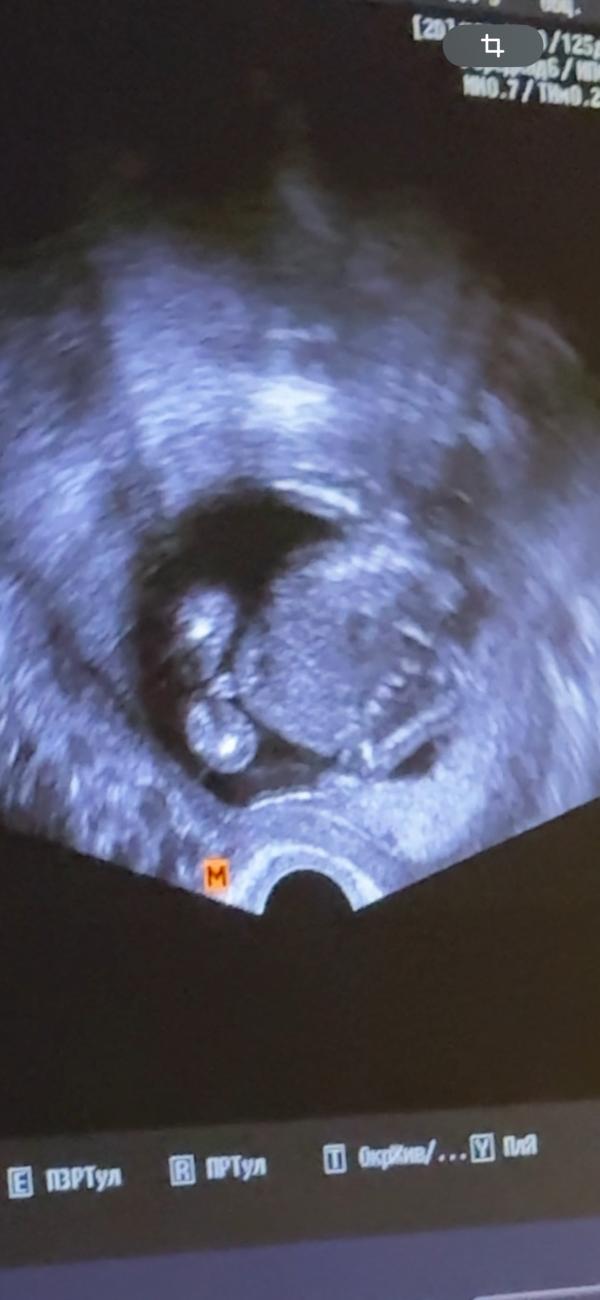

По узи 16-17 недель

Сказали ПРЕДПОЛОЖИТЕЛЬНО мальчик

Мне тоже кажется,что мужское видно))

На ваш взгляд и опыт,кто?😊

Хрен знает, ракурс неправильный. Как поняла на фото животик и ножки

Я прям вижу, что это пуповина между ножек

Мне тоже говорили предположительно, но думали и пуповина между ног встала, подтвердили мальчика только на 2 скрининге, так что лучше не загадывайте, а ждите точного результата)